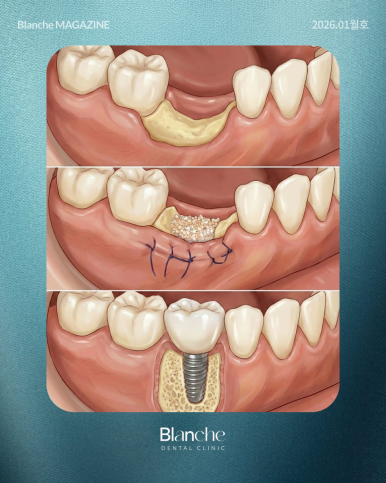

뼈이식을 하는 이유는 임플란트라는 나사를 지탱해 줄 '뼈의 양'이 부족하기 때문입니다.

나사가 잇몸뼈 밖으로 노출되면 세균 감염에 취약해지고 결국 임플란트가 빠질 수 있는데요.

이를 방지하기 위해 뼈가 얇거나 높이가 낮은 경우에만 보충해 주는 것이 뼈이식의 본질입니다.

뼈이식은 몸에 이물질을 넣는 과정인 만큼, 꼭 필요한 경우에만

최소한으로 진행하는 것이 가장 건강한 진료입니다.